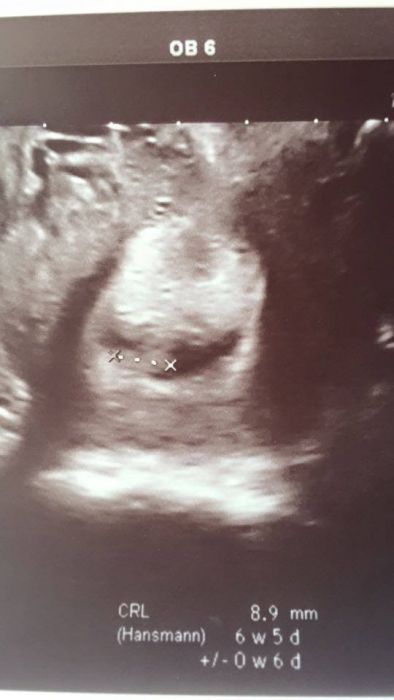

Ženy zapoměla jsem Vám sem přihodit fotku z minulého týdne. konec sedmého týdne. Manžel říká, že prej tam leží, jako já v posteli. Já tomu říkám ( poloha do penálu ) :-D. Tak mrknětě, další budu mít příští týden. Jinak na screening jdu 21.12., takže to doufejme bude dáreček k vánocům :-). Jste už někdo objednaný? Mají tam docela plno před svátkama :-/